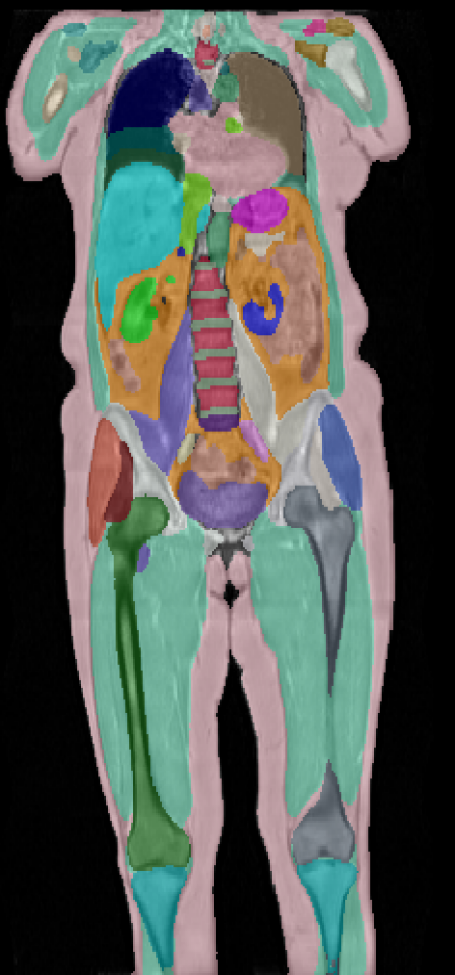

\captionof

figureUKBOB Size and Diversity. Our proposed UK Biobank Organs and Bones (UKBOB) is the largest labeled medical imaging dataset for segmentation, comprising body organs of 51,761 MRI 3D samples (17.9 M 2D images) and a total of more than 1.37 billion 2D masks of 72 organs. Left: we show label examples from UKBOB from axial, coronal, and sagittal views. Right: We show a plot of the size (number of 2D images) and diversity (number of classes) of our UKBOB compared to other medical images datasets. The size of the bubbles indicates 2D image resolution. This new scale in dataset size and diversity should unlock a new wave of applications and methods in the computer vision and medical imaging communities.